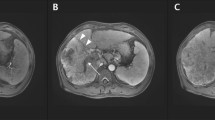

A–J After infection with hsa_circ_0007456-overexpressing or shRNA lentivirus or the control lentivirus in SMMCC-7721 or QGY-7703, the relative RNA levels of ICAM-1 were detected by RT-qPCR (A–D); the expression of ICAM-1 (CD107a) on the cell surface was detected by flow cytometry (E, F); and the relative protein levels of ICAM-1 were detected by western blotting (G–J). K, L SMMCC-7721 or QGY-7703 stably expressing the luciferase construct containing the wild-type (WT) or mutant (MT) ICAM-1 were respectively infected with hsa_circ_0007456-overexpressing or shRNA lentivirus or the negative control lentivirus (NC), and then the luciferase activity was examined. M–R After treatment with the indicated hsa_circ_0007456 or the control lentivirus plus miR-6852-3p mimic or negative control (NC) in SMMCC-7721 or QGY-7703, the mRNA levels (M, N) and the protein levels (O–R) of ICAM-1 were respectively detected by RT-qPCR and western blotting. Data are representative of three independent experiments and are presented as mean ± SD. **p < 0.01.